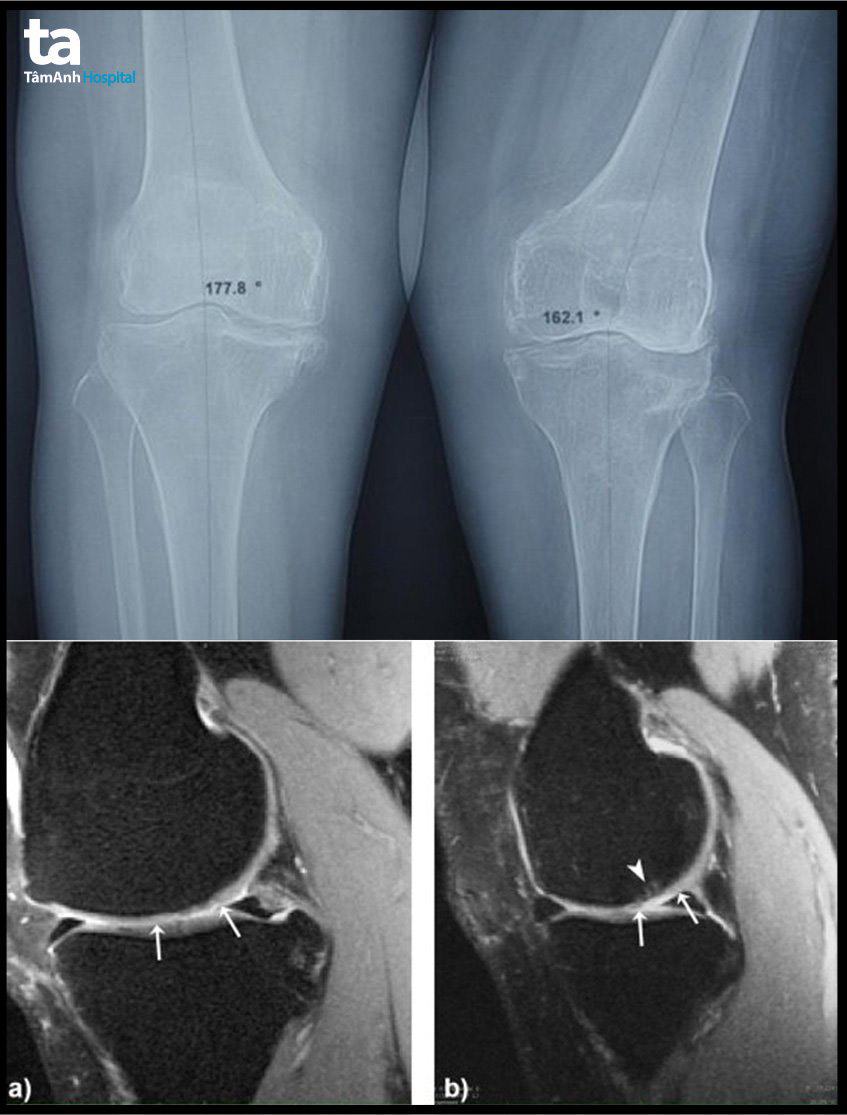

Thoái hóa khớp gối hiện là một trong những bệnh viêm khớp phổ biến nhất, là hậu quả của quá trình cơ học và sinh học làm mất cân bằng giữa tổng hợp – hủy hoại của sụn và xương dưới sụn. Sự mất cân bằng này có thể đến từ nhiều yếu tố như: di truyền, tuổi tác, chuyển hóa và chấn thương. Trước đây, bệnh thường tấn công người già nhưng hiện nay đang có xu hướng ngày càng trẻ hóa, trở thành một trong những gánh nặng y tế trên toàn cầu.

Với chủ đề: “Điều trị toàn diện thoái hóa khớp gối từ Nội khoa đến Ngoại khoa”, Hội thảo nhằm chia sẻ, cập nhật những tiến bộ, kỹ thuật mới nhất cũng như những kinh nghiệm thực tiễn trong việc điều trị thành công thoái hóa khớp gối bằng nội khoa lẫn ngoại khoa tại Hệ thống Bệnh viện Đa khoa Tâm Anh.

| 10:35 – 10:55 | Đục xương chỉnh trục trong điều trị thoái hóa khớp gối | ThS.BSCKI Lê Đình Khoa |